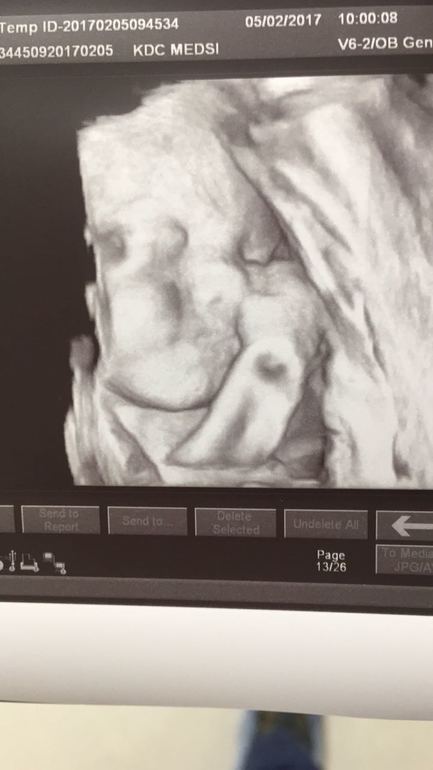

А ваши дети похожи с фото УЗИ?

Вопросы про УЗИ, обследования и анализы: что, где, как, когда?Чисто любопытство. У меня фото малыша с 19 недель, уже и 10 недель прошло, а я все смотрю и не пойму, где что на фото. Вроде и не мутное, но нет четкого контура ни губ, ни подбородка. Вот думаю, фото такое что-ли? И не представляю какой он будет в жизни. Просто все говорят, что как на УЗИ так и в жизни. А у вас как?

Нам дали снимок 3д на 21 недели, личико отлично видно и черты лица... Все говорят на мужа похож) я сразу сказала мужу, еще на экране когда показали, смотри твоя копия))😊 вот посмотрим потом, сравним))😊

Вот мы в 26 недель. С младшей оч похожи, посмотрим как на самом деле будет.)